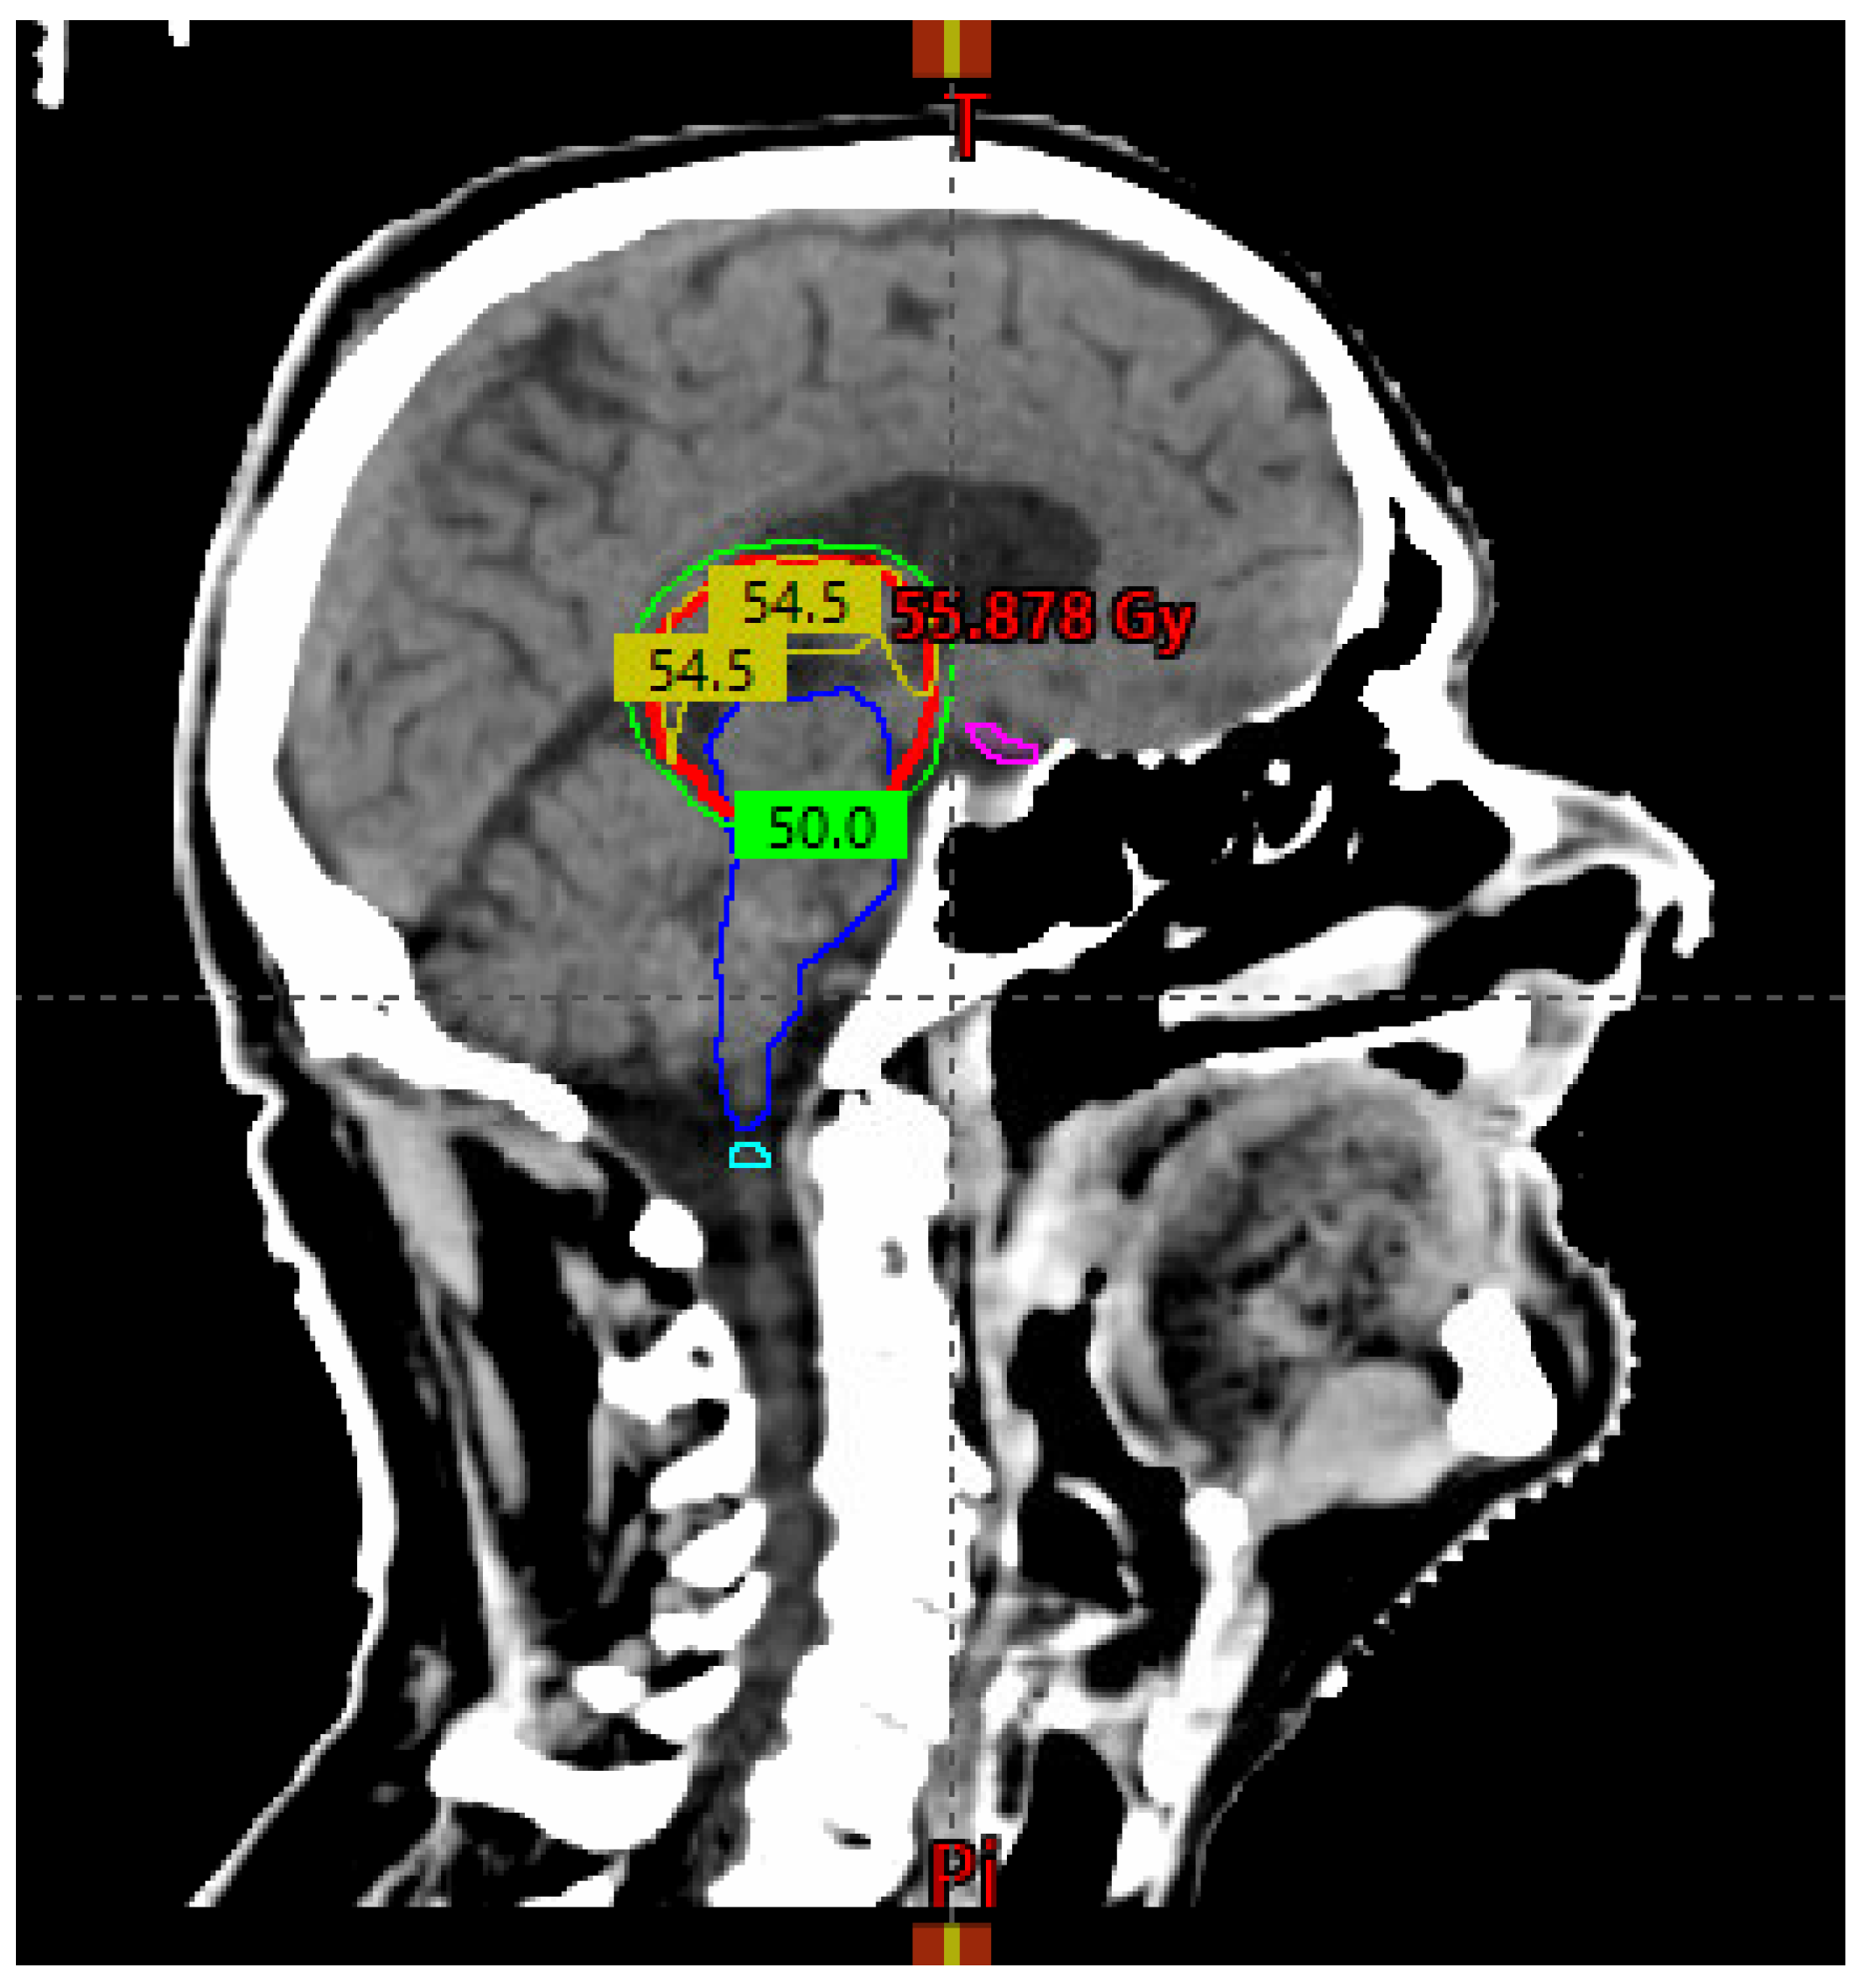

| Treatment Parameter | Definition |

|---|---|

| GTV | Residual disease based on pre-and post-op imaging |

| CTV | GTV + tumor bed on planning CT and MRI + 5 mm margin cropped to anatomic boundaries* |

| PTV | CTV + 5 mm concentric margin |

| Dose and fractionation | 54 Gy / 30 fractions delivered Monday to Friday over six weeks in 1.8 Gy once daily fractions |

| Organs at risk | Dose constraint (to organ at risk + 3 mm concentric margin) |

| Brainstem | V54 Gy < 0.03 cc |

| Spinal cord | V45 Gy < 0.03 cc |

| Optic chiasm | V54 Gy < 0.03 cc |

| Optic nerves | V54 Gy < 0.03 cc |

| Brain | V60Gy < 33%, V50Gy < 66% |

| Eyes | V45 Gy < 0.03 cc |